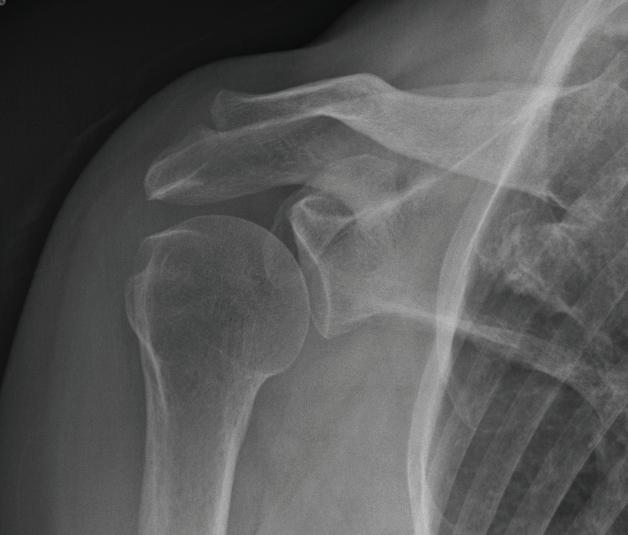

Figure 1-6 is an example of a common posterior oblique projection of the shoulder, described by Grashey

FIGURE 1-6 Grashey (oblique shoulder) view radiograph (top) and a schematic drawing of patient orientation for the Grashey view (bottom).